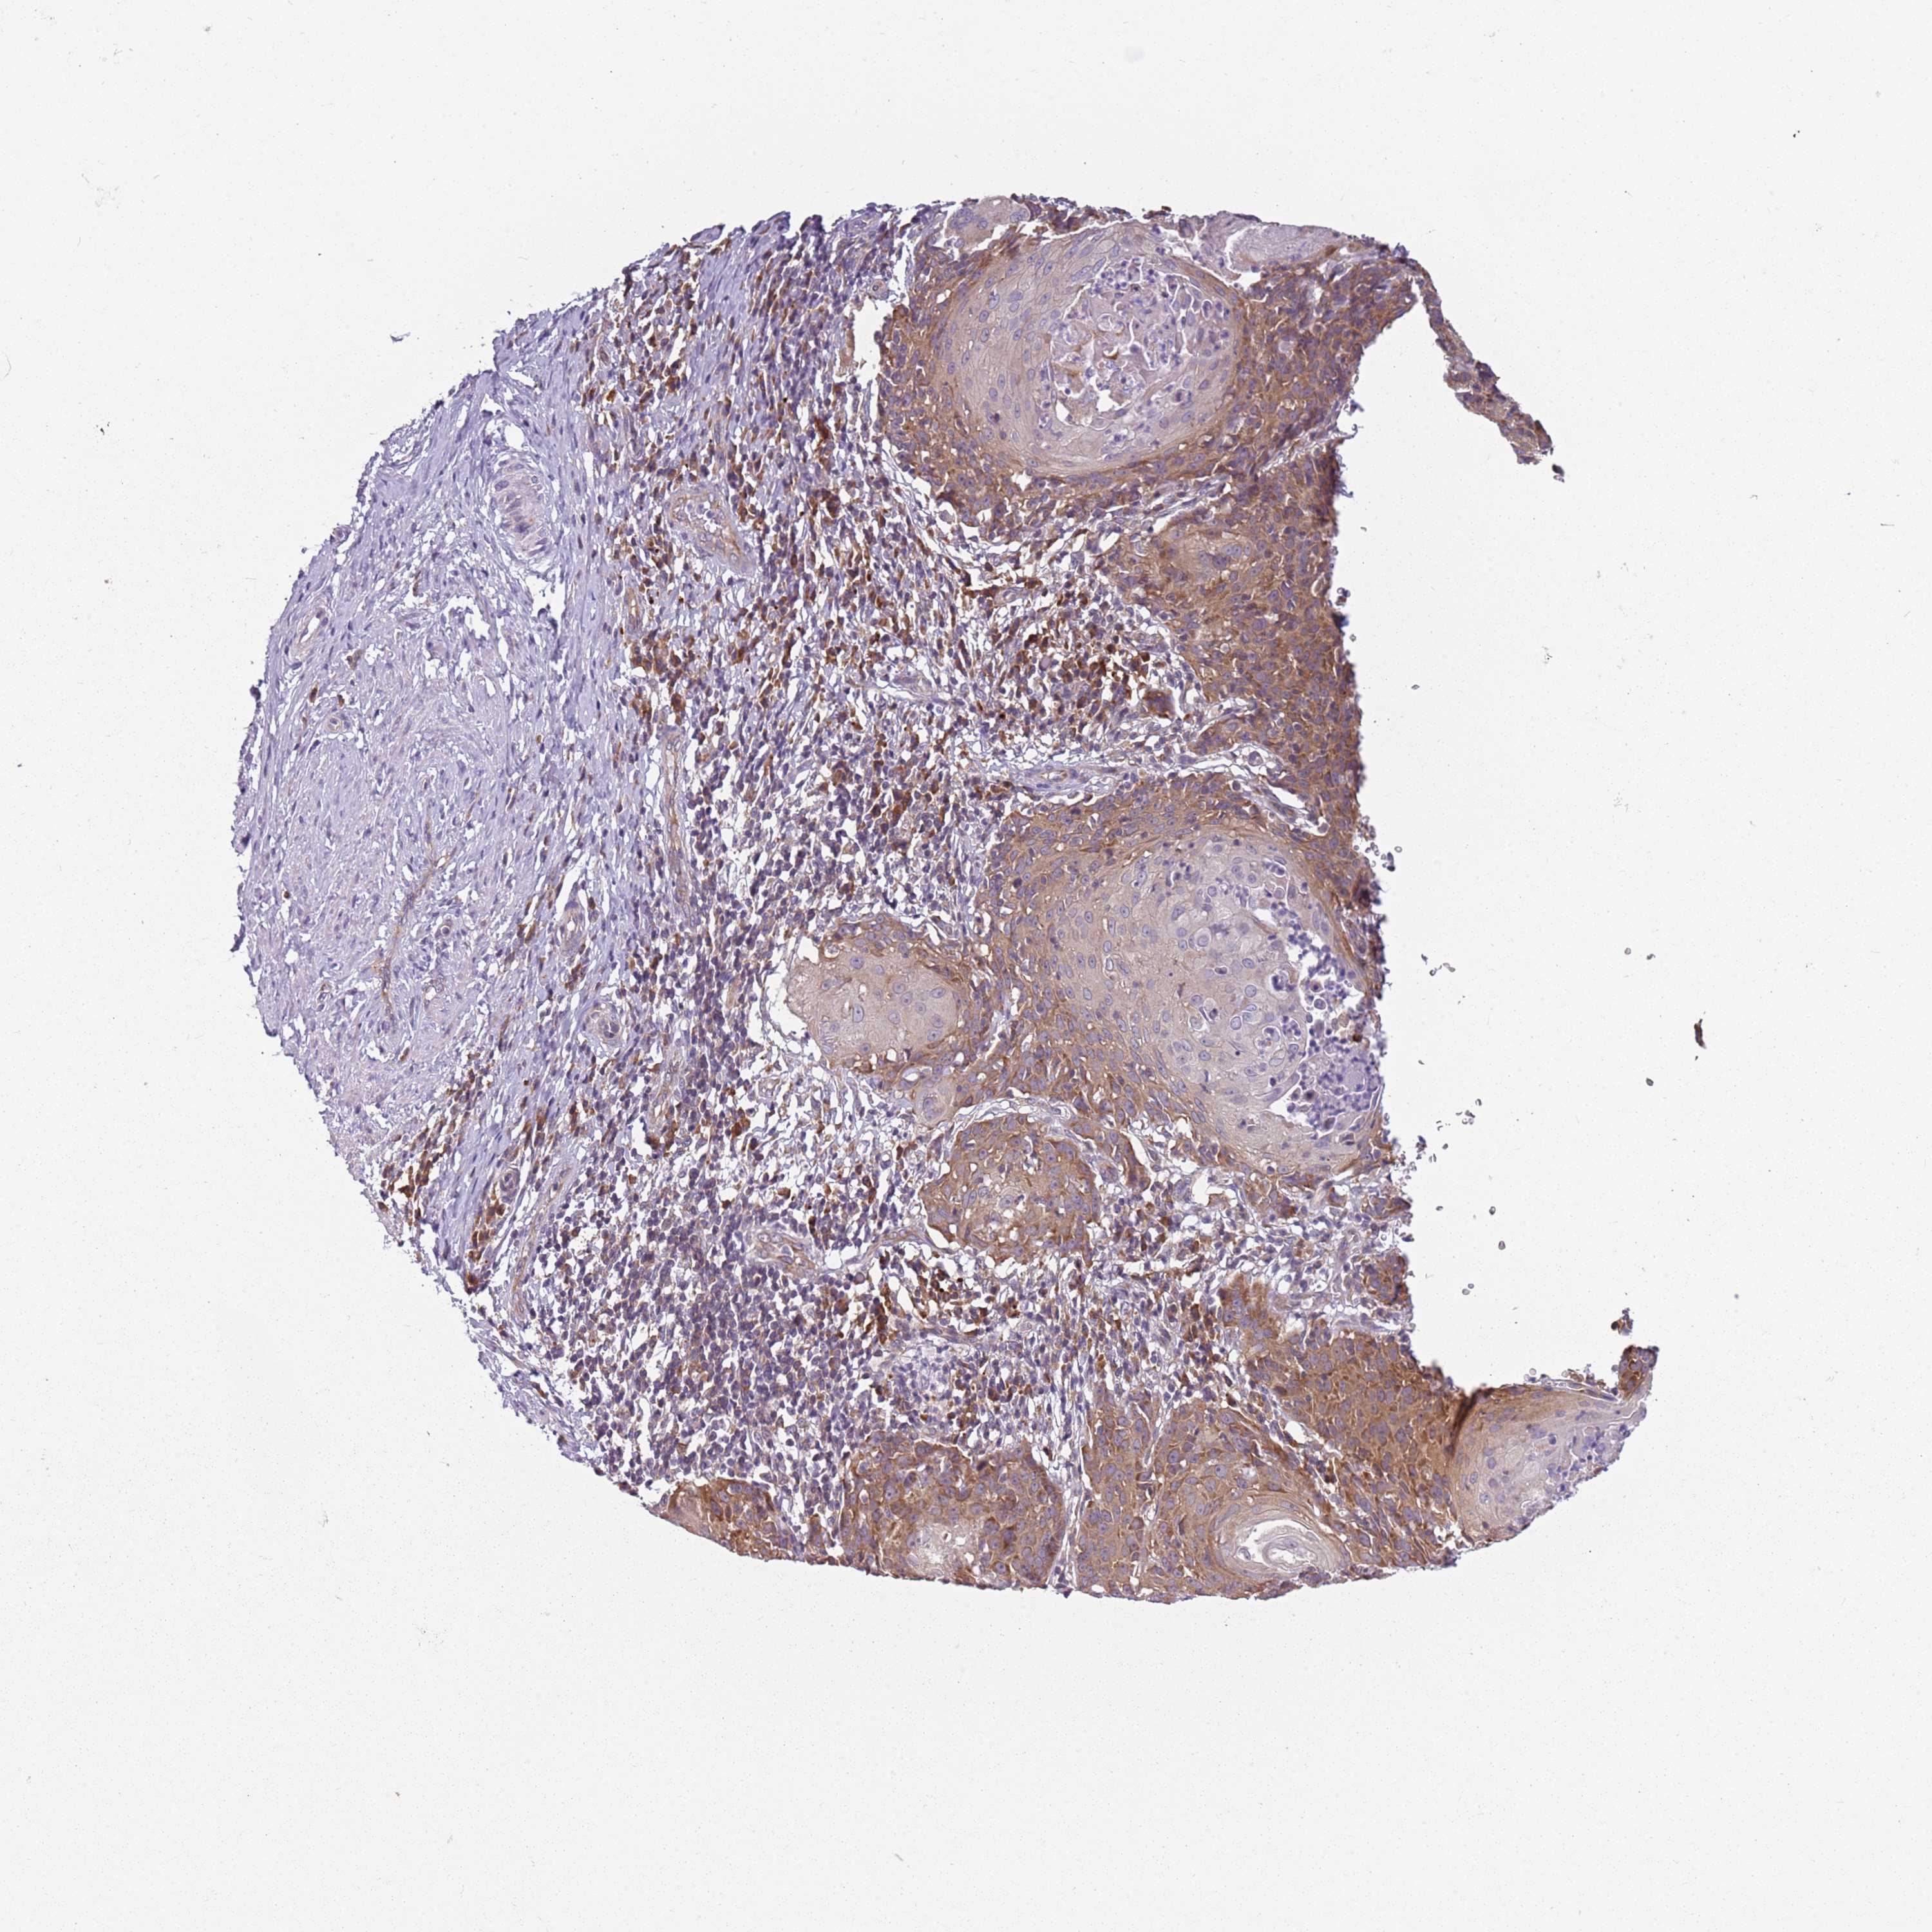

CERVICAL CANCER - Protein expressioni

A mouse-over function shows sample information and annotation data. Click on an image to view it in a full screen mode. Samples can be filtered based on level of antibody staining by selecting one or several of the following categories: high, medium, low and not detected. The assay and annotation is described here.

Note that samples used for immunohistochemistry by the Human Protein Atlas do not correspond to samples in the TCGA dataset.

Antibody stainingi

Antibody staining in the annotated cell types in the current human tissue is reported as not detected, low, medium, or high, based on conventional immunohistochemistry profiling in selected tissues. This score is based on the combination of the staining intensity and fraction of stained cells.

Each image is clickable and will lead to virtual microscopy that enables deeper exploration of all samples and also displays staining intensity scores, fraction scores and subcellular localization as well as patient and tissue information for each sample.

Antibody HPA047132

Staining

High

Medium

Low

Not detected

Intensity

Strong

Moderate

Weak

Negative

Quantity

>75%

75%-25%

<25%

None

Location

Nuclear

Cytoplasmic/membranous

Cytoplasmic/membranous,nuclear

Squamous cell carcinoma, NOS

Adenocarcinoma, NOS